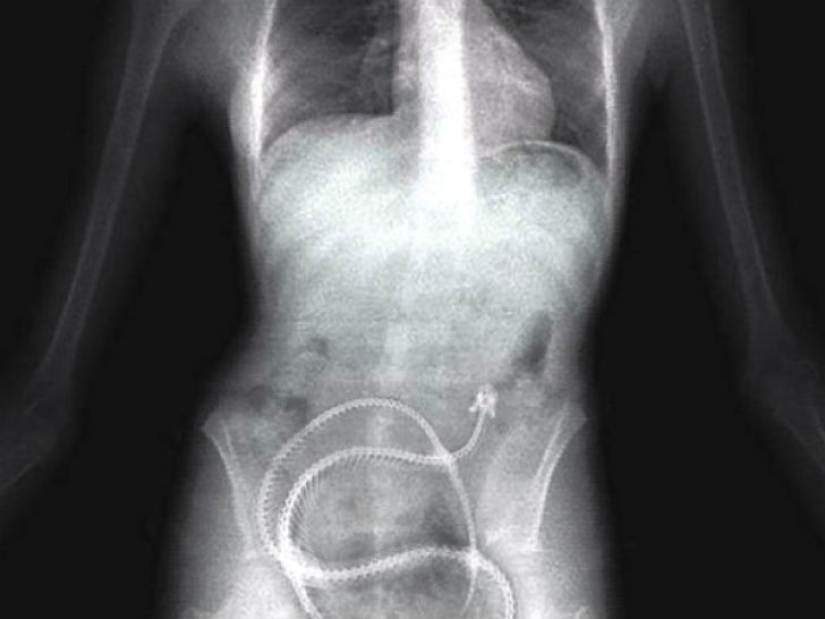

Some prisoners are ready to swallow anything to get out of prison, for example, to the hospital — even the springs from the mattress.